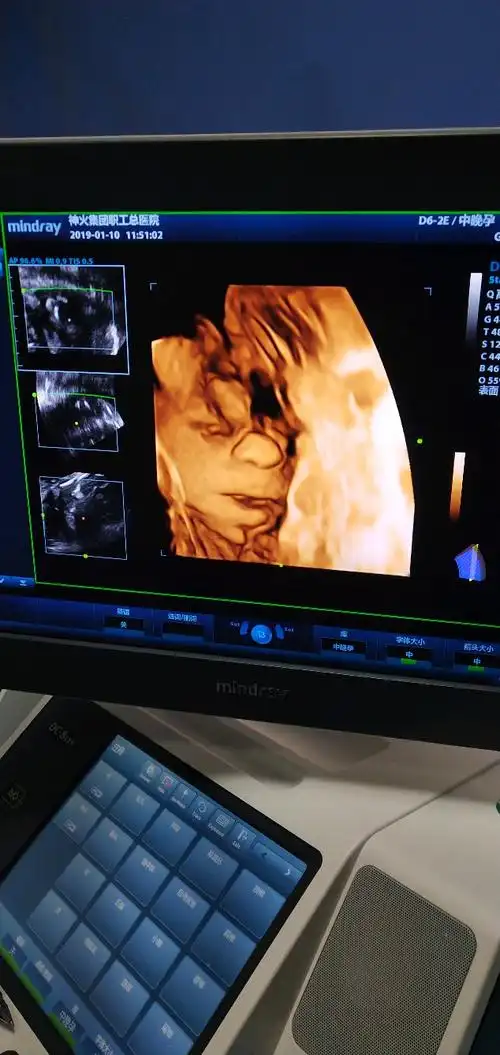

四维彩超和宝宝的长相差别大吗?这些特征存在误差,丑俊难辨

被宝宝的四维彩超照丑哭了?不是医生技术不好,而是有客观原因的

四维彩超回来,感觉宝宝好丑啊!

为什么胎儿四维照"丑相"?b超医生告诉你真相,原因是这三点